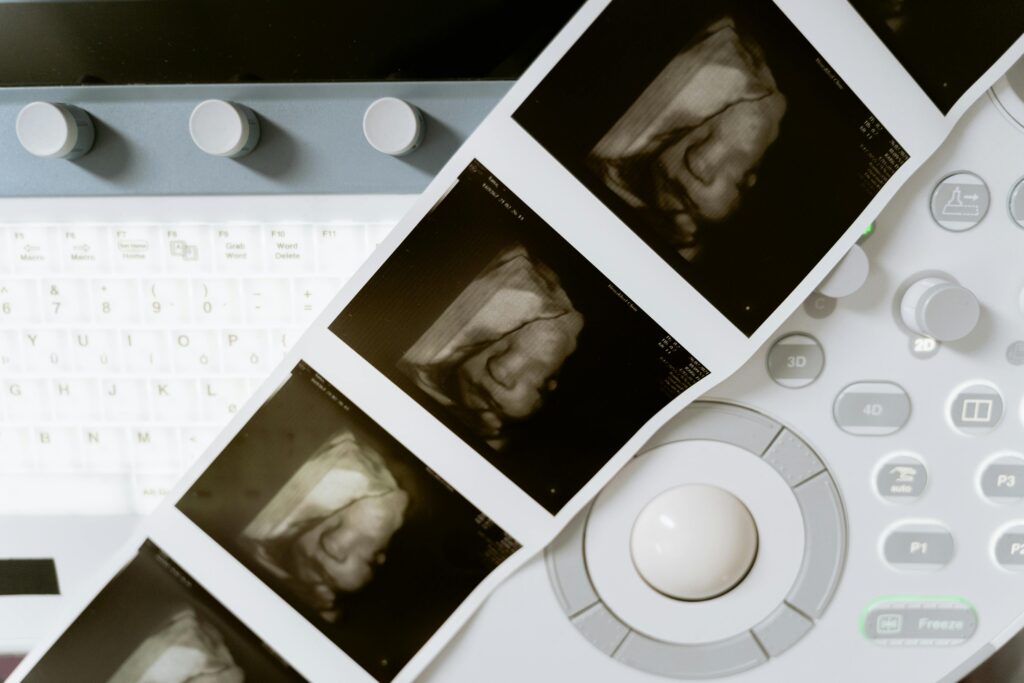

- Atypical ultrasound images.

NIPT analyzes small fragments of fetal DNA in maternal blood to detect certain chromosomal abnormalities safely. With recent advancements, NIPT can also be used to determine paternity during pregnancy. It filters certain conditions in the chromosomes and is said to be very sensitive to some abnormalities. It does not involve any direct harm to the pregnancy because it is only necessary to draw blood.